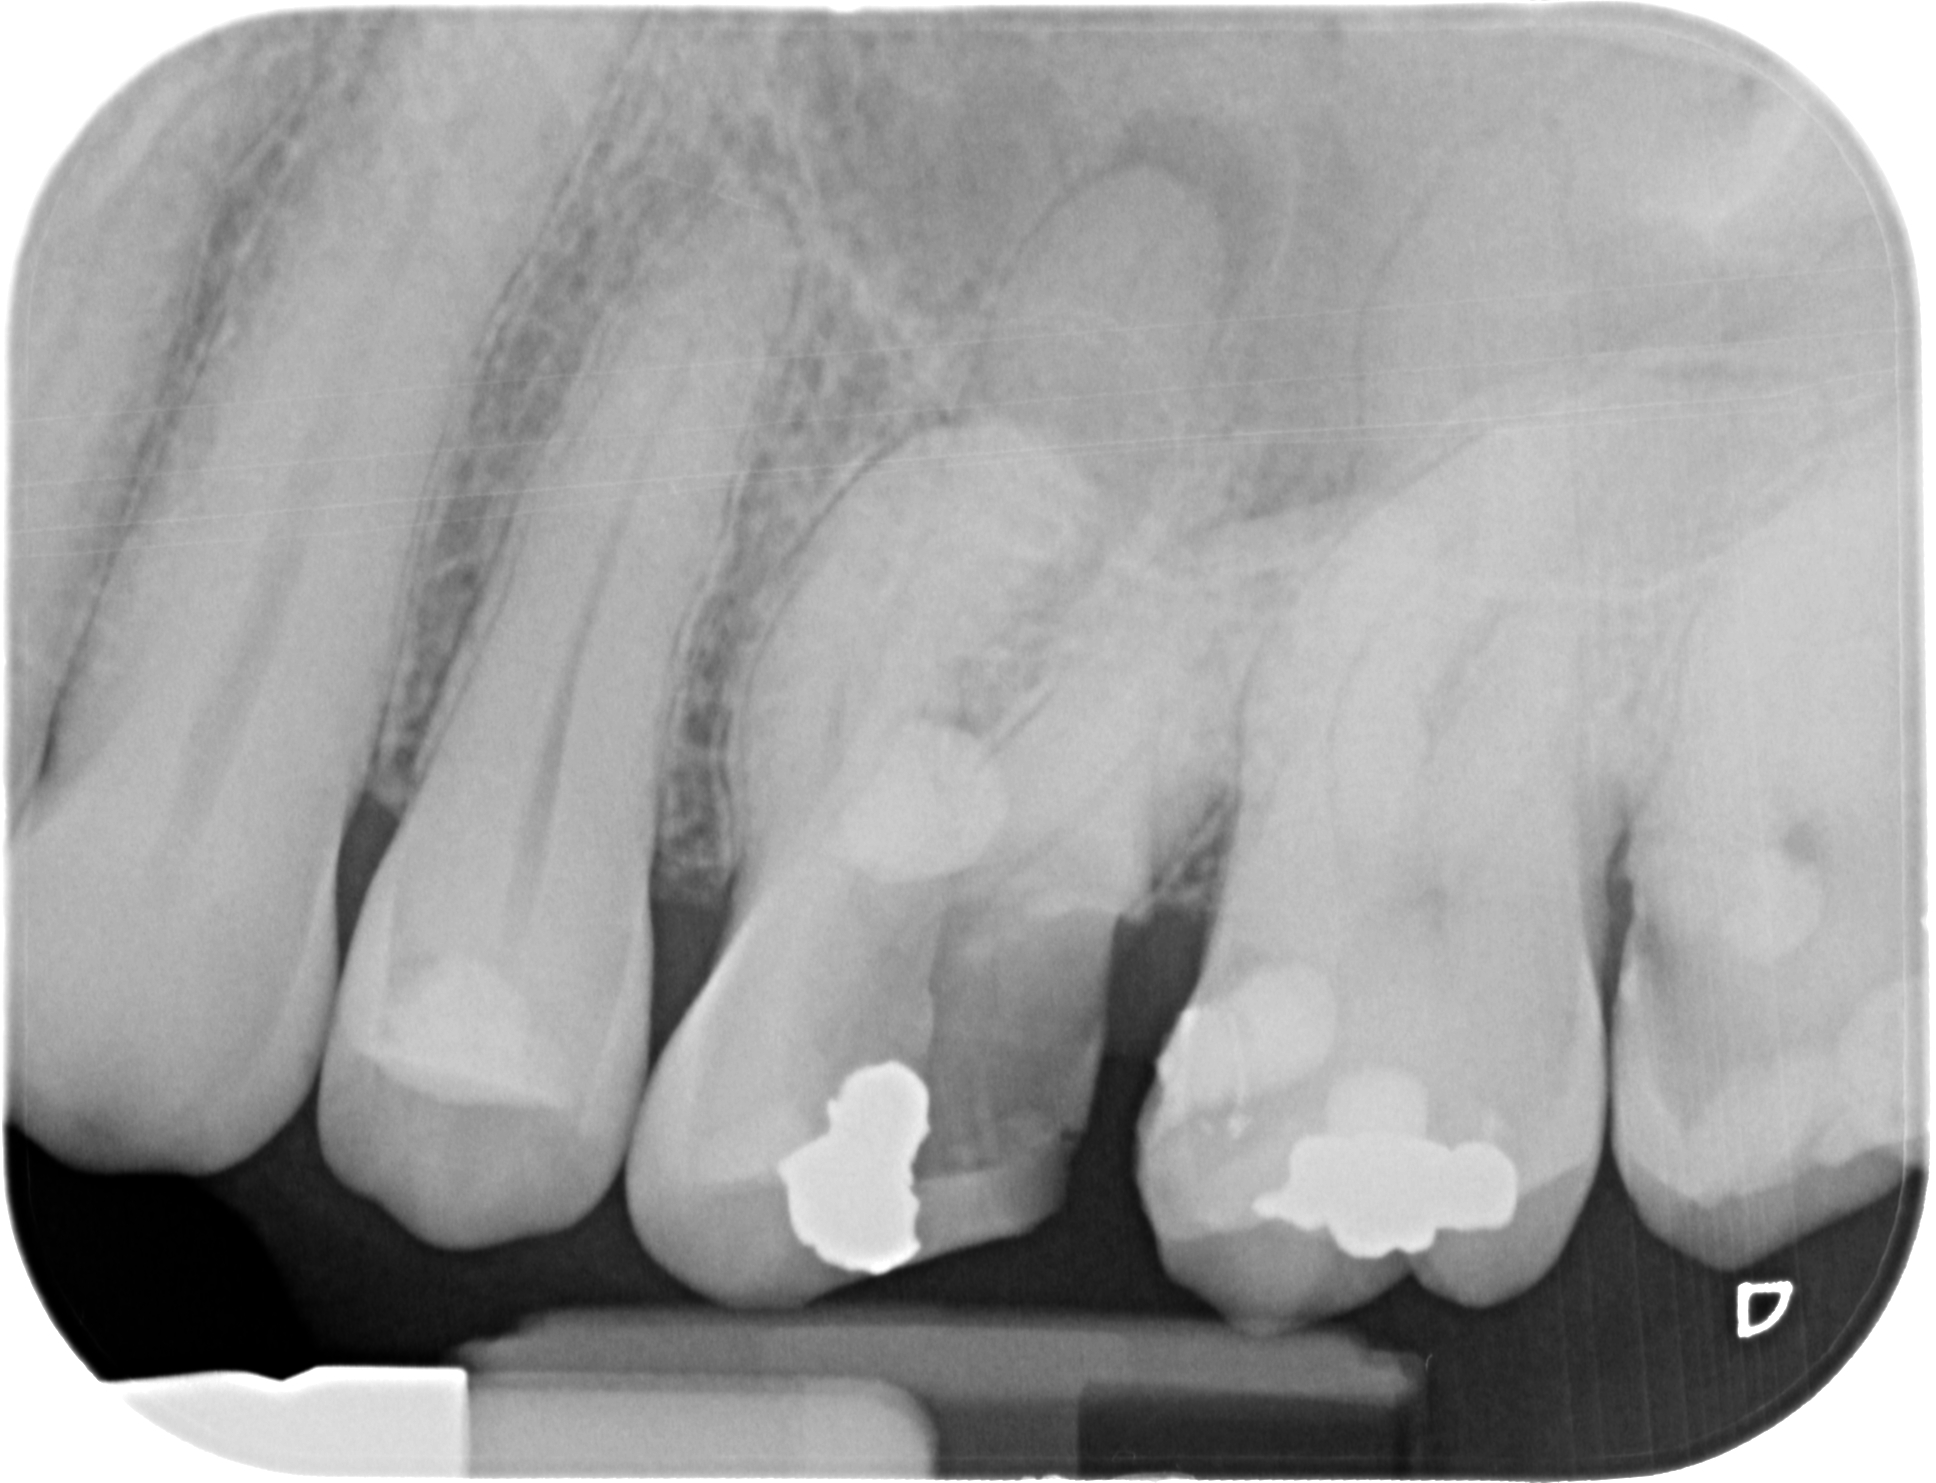

La Endodoncia es la especialidad que permite conservar el diente en boca cuando la patología pulpar del diente es ya irreversible.

Durante una endodoncia, vulgarmente conocida como “matar el nervio”, lo que hacemos es eliminar el tejido pulpar (el nervio) enfermo y conformar y desinfectar todo el sistema de conductos radiculares, para luego rellenar y sellar esos conductos de un material termoplástico. A continuación hay que Reconstruir la corona mediante técnicas adhesivas, bien con composite o si la reconstrucción es muy grande, recurrimos a la Porcelana como mejor material para restituir la integridad funcional y anatómica perdida.